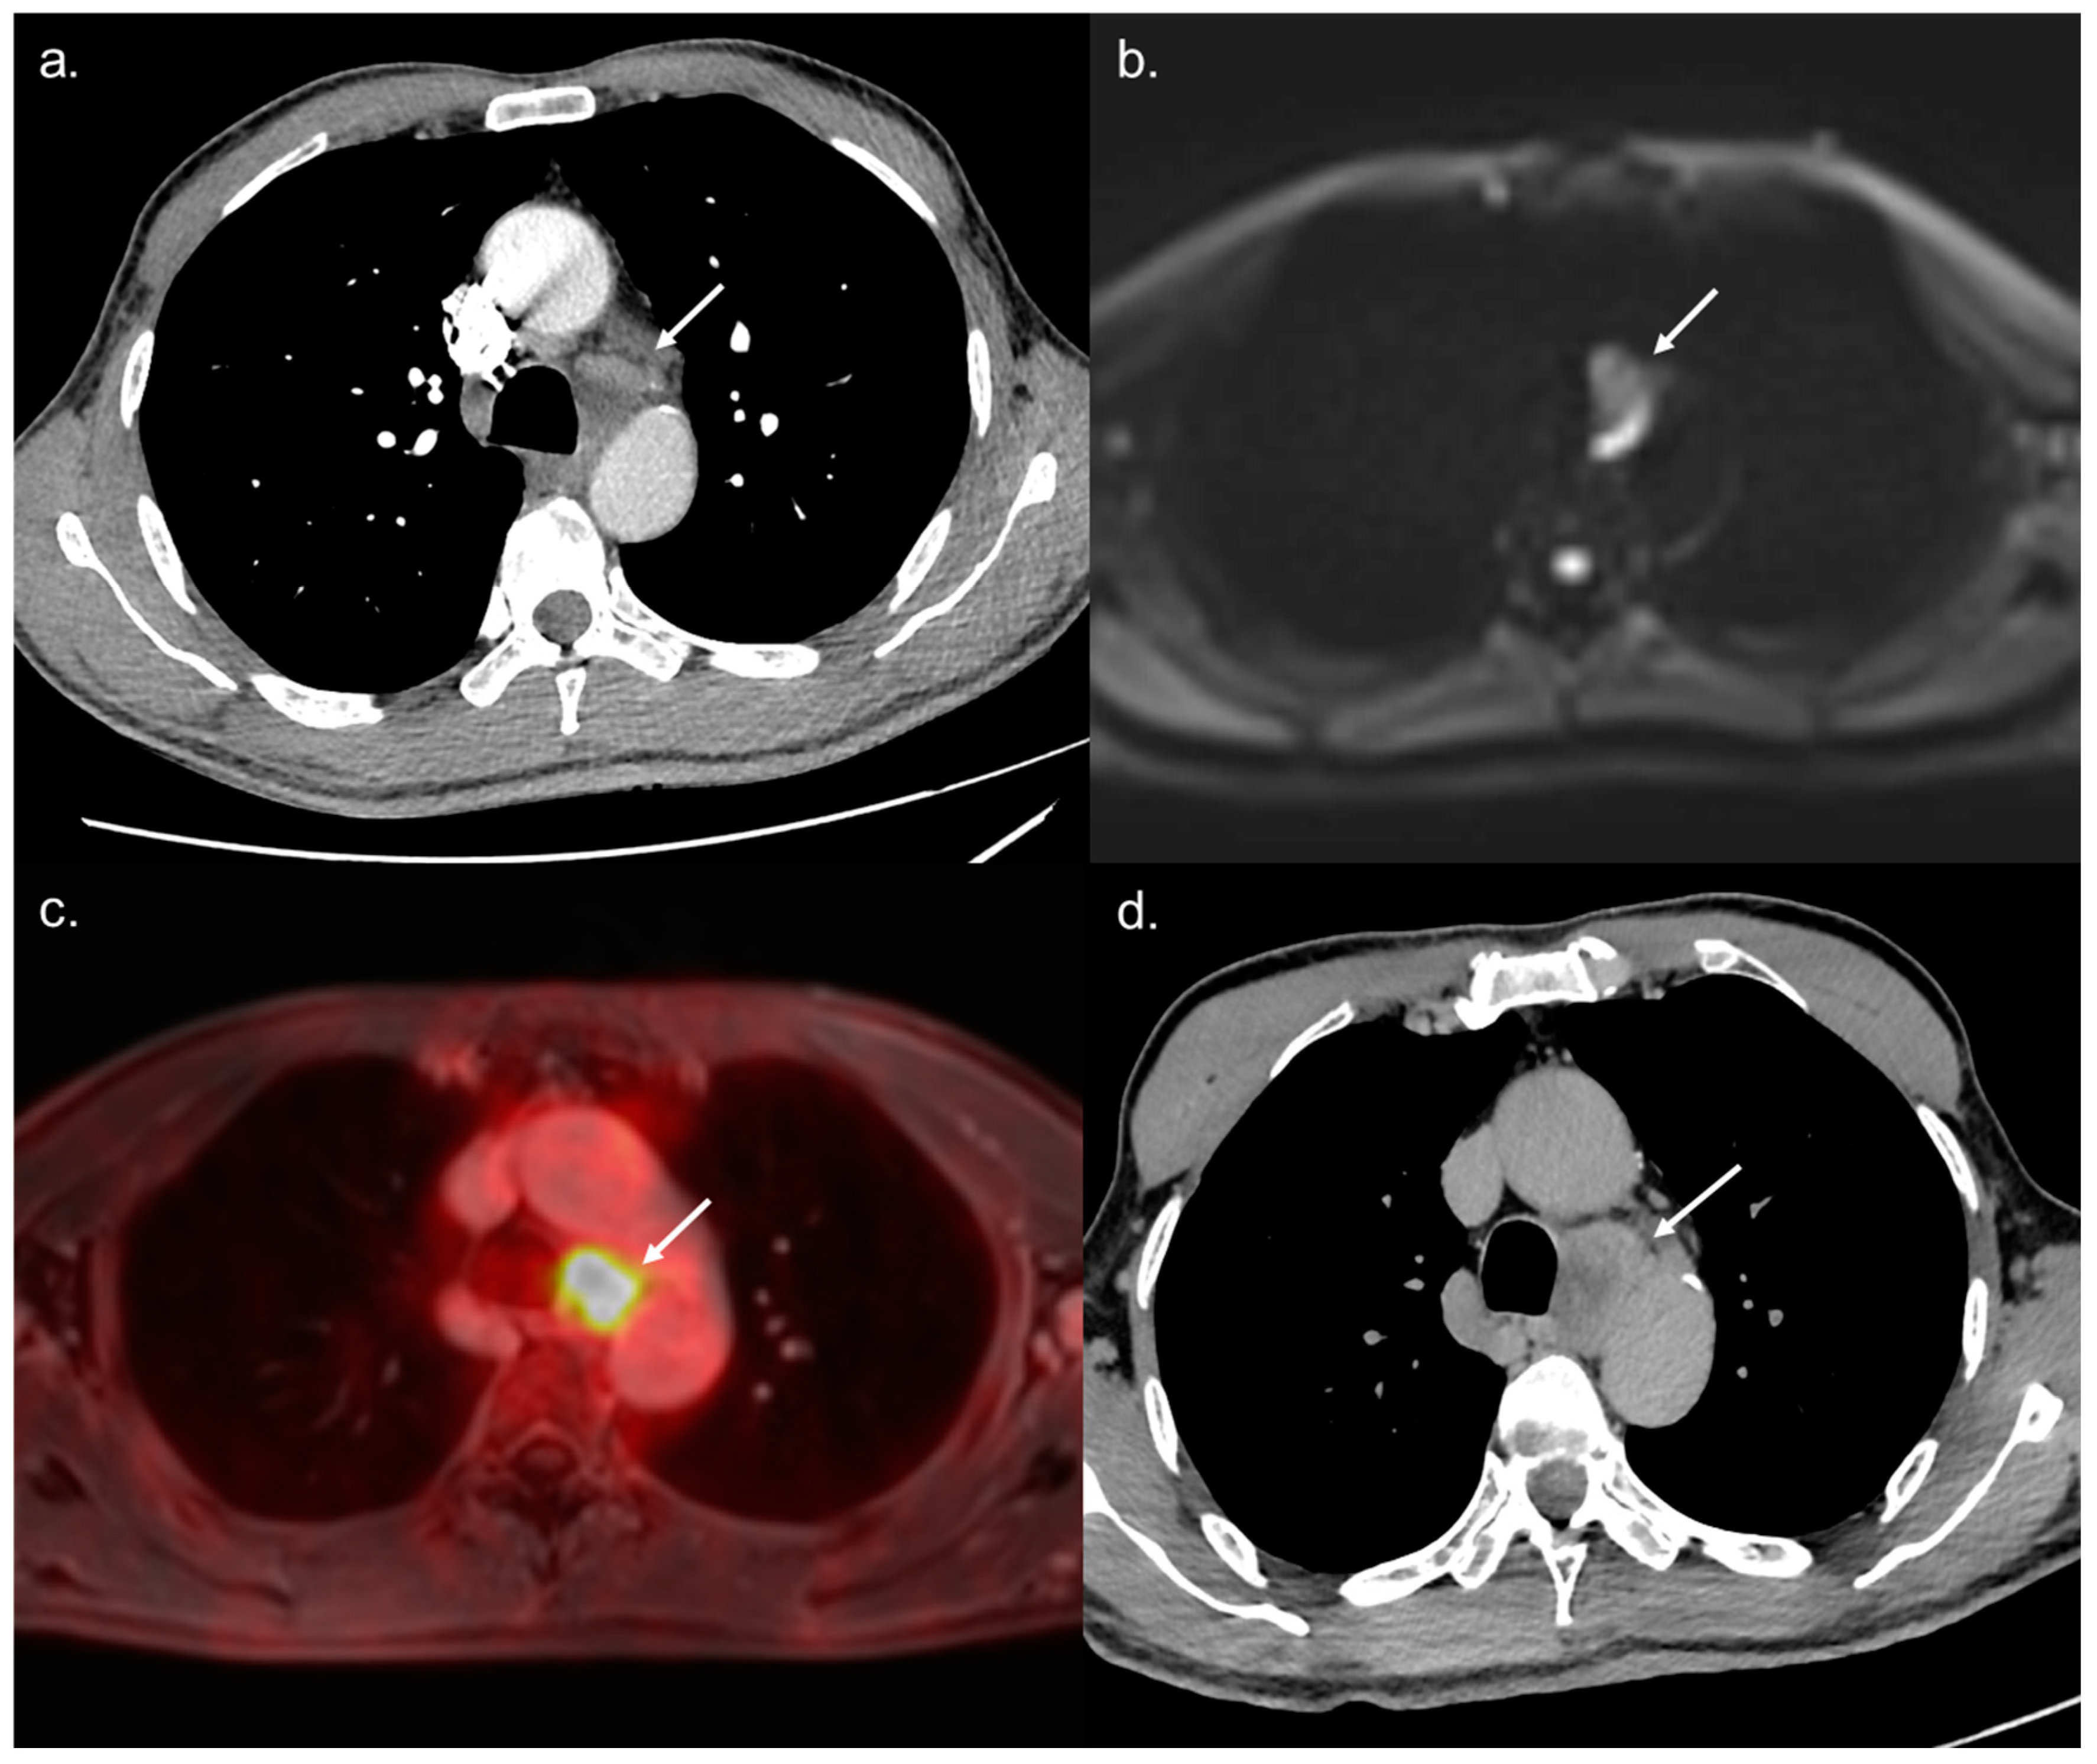

Figure 4. A 68-year-old BCLC C patient referred to WB-PET/MRI before TARE. The CT-CAP performed (a) showed a 12 × 25 mm large mediastinal lymph node of indeterminate nature. The WB-PET/MRI revealed hyperintensity on b800 s/mm2 DWI (b) with hypermetabolism on 18F-FDG-PET (c) suggestive of metastatic involvement. Followup performed two months later confirmed the metastatic nature of the lymph nodes with rapid increase in size and necrosis (d).

All 14 metastatic sites were correctly identified on the WB-PET/MRI, although only 7 of 16 individual pulmonary metastases (44%) were seen (Figure 2). On the CT-CAP/liver MRI dataset, six metastatic sites were correctly identified (6/14; 43%), resulting in a significantly lower sensitivity (43% vs. 100%, p = 0.002). Notably, all 10 individual bone metastases were missed on the CT-CAP/liver MRI (Figure 3), as well as two mediastinal lymph nodes (Figure 4) and one retroperitoneal lymph node involvement (Figure 3).

The WB-PET/MRI lead to changes in therapeutic management in 10 of 104 patients (9.6%). Metastatic lesions were identified by the WB-PET/MRI in two BCLC stage C patients referred before liver transplantation (Figure 3) and in five BCLC stage C patients referred before TARE (Figure 2 and Figure 4).